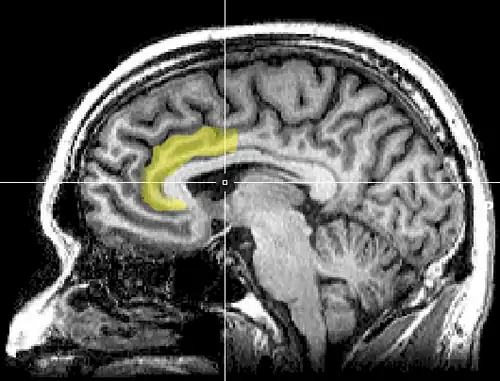

Brain imaging techniques including magnetic resonance imaging (MRI), functional magnetic resonance imaging (fMRI), and positron emission tomography (PET) have shown that there are two main areas in the brain that are involved in the processing of the Stroop task.[9][10] They are the anterior cingulate cortex, and the dorsolateral prefrontal cortex.[11] More specifically, while both are activated when resolving conflicts and catching errors, the dorsolateral prefrontal cortex assists in memory and other executive functions, while the anterior cingulate cortex is used to select an appropriate response and allocate attentional resources.[12]

The posterior dorsolateral prefrontal cortex creates the appropriate rules for the brain to accomplish the current goal.[12] For the Stroop effect, this involves activating the areas of the brain involved in color perception, but not those involved in word encoding.[13] It counteracts biases and irrelevant information, for instance, the fact that the semantic perception of the word is more striking than the color in which it is printed. Next, the mid-dorsolateral prefrontal cortex selects the representation that will fulfill the goal. The relevant information must be separated from irrelevant information in the task; thus, the focus is placed on the ink color and not the word.[12] Furthermore, research has suggested that left dorsolateral prefrontal cortex activation during a Stroop task is related to an individual's’ expectation regarding the conflicting nature of the upcoming trial, and not so much on the conflict itself. Conversely, the right dorsolateral prefrontal cortex aims to reduce the attentional conflict and is activated after the conflict is over.[11]

Moreover, the posterior dorsal anterior cingulate cortex is responsible for what decision is made (i.e. whether someone will say the written word or the ink color).[11] Following the response, the anterior dorsal anterior cingulate cortex is involved in response evaluation—deciding whether the answer is correct or incorrect. Activity in this region increases when the probability of an error is higher.[14]